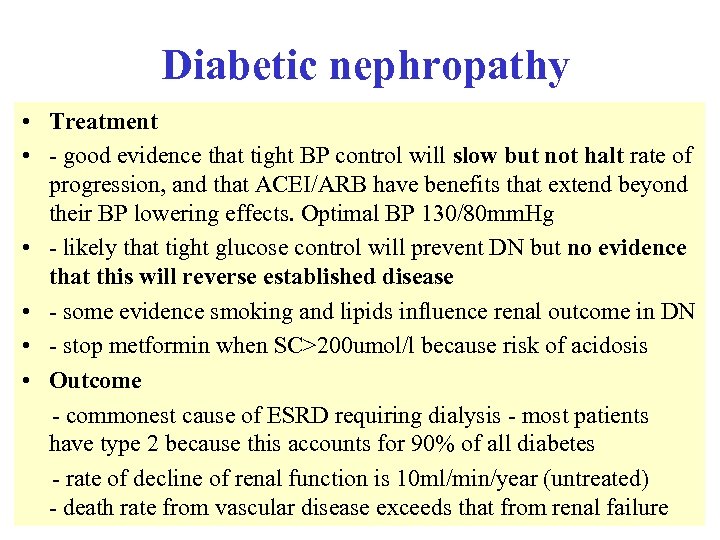

Diabetic nephropathy • Treatment • - good evidence that tight BP control will slow but not halt rate of progression, and that ACEI/ARB have benefits that extend beyond their BP lowering effects. Optimal BP 130/80 mm. Hg • - likely that tight glucose control will prevent DN but no evidence that this will reverse established disease • - some evidence smoking and lipids influence renal outcome in DN • - stop metformin when SC>200 umol/l because risk of acidosis • Outcome - commonest cause of ESRD requiring dialysis - most patients have type 2 because this accounts for 90% of all diabetes - rate of decline of renal function is 10 ml/min/year (untreated) - death rate from vascular disease exceeds that from renal failure

Diabetic nephropathy • Treatment • - good evidence that tight BP control will slow but not halt rate of progression, and that ACEI/ARB have benefits that extend beyond their BP lowering effects. Optimal BP 130/80 mm. Hg • - likely that tight glucose control will prevent DN but no evidence that this will reverse established disease • - some evidence smoking and lipids influence renal outcome in DN • - stop metformin when SC>200 umol/l because risk of acidosis • Outcome - commonest cause of ESRD requiring dialysis - most patients have type 2 because this accounts for 90% of all diabetes - rate of decline of renal function is 10 ml/min/year (untreated) - death rate from vascular disease exceeds that from renal failure